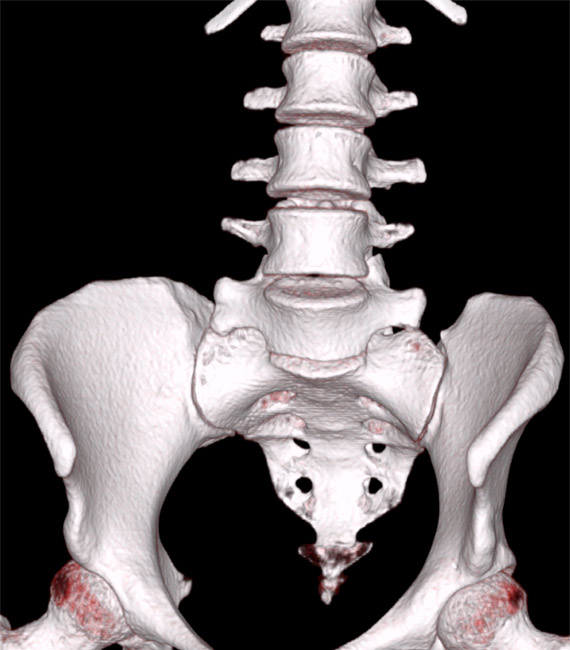

Introducerea tehnicii de achiziție spirală, care a permis achiziția continuă și rapidă a unui volum de date uriaș, cu posibilitatea de reconstrucție ulterioară în orice plan, nu doar cel transversal, precum și cu posibilitatea de reconstrucții tridimensionale spectaculoase. Inițial, achiziția se făcea doar în modul secvențial: după o rotație de 360 de grade a tubului, masa cu pacientul avansa în interiorulul aparatului cu grosimea unui slice (de obicei 10mm) și se făcea o noua achiziție. Acest mod este mai lent și nu permite reconstrucții în alt plan la fel de ușor ca achiziția spirală, la care tubul se învârte continuu, iar masa se mișca și ea în același timp. În prezent, achiziția secvențială se mai utilizează de rutină numai la examinarea cerebrală.

Algoritmii de reconstrucție sunt din ce în ce mai buni, putând reprezenta tot mai exact anatomia internă a corpului, cu iradiere din ce în ce mai mică. Reconstrucțiile tridimensionale devin mai exacte decât atlasele de anatomie și în felul acesta un extraordinar material didactic pentru studenți și rezidenți.

Evolutia calculatoarele permite in prezent prelucrari complexe ale imaginii achizitionate, pe console speciale, fara a mai fi nevoie de prezenta pacientului. Astfel, imaginile sursa sub forma unui volum impresionant de date ce acopera o anumita regiune a corpului pot fi prelucrate in multiple moduri: